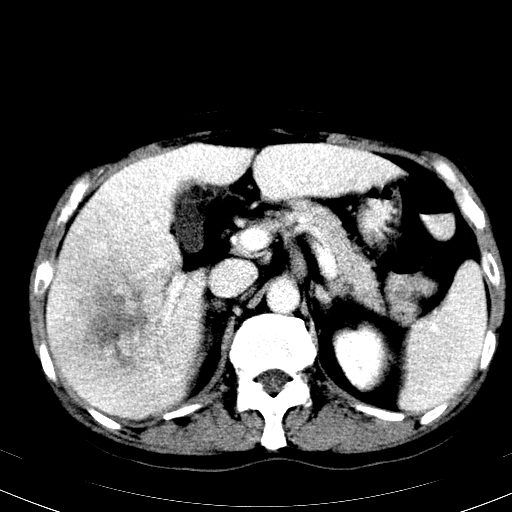

以下是引用卜一在2008-6-23 15:38:00的发言:[br]本例延时期的图象未扫完,单纯平扫 动脉期及门脉期特征分析:平扫低密度较大肿块,内见不规则出血灶,界限清楚。动脉期边缘结节样强化,门脉期病灶边缘进一步强化并范围明显缩小。因此考虑:血管瘤伴出血!

以下是引用深泽交通医院在2008-6-23 16:40:00的发言:[br]考虑肝癌伴出血.诊断依据:平扫瘤壁结节密度低于肝实质,动脉期壁结节明显强化,门脉期略低于肝实质密度[br]病灶有明显的假包膜,